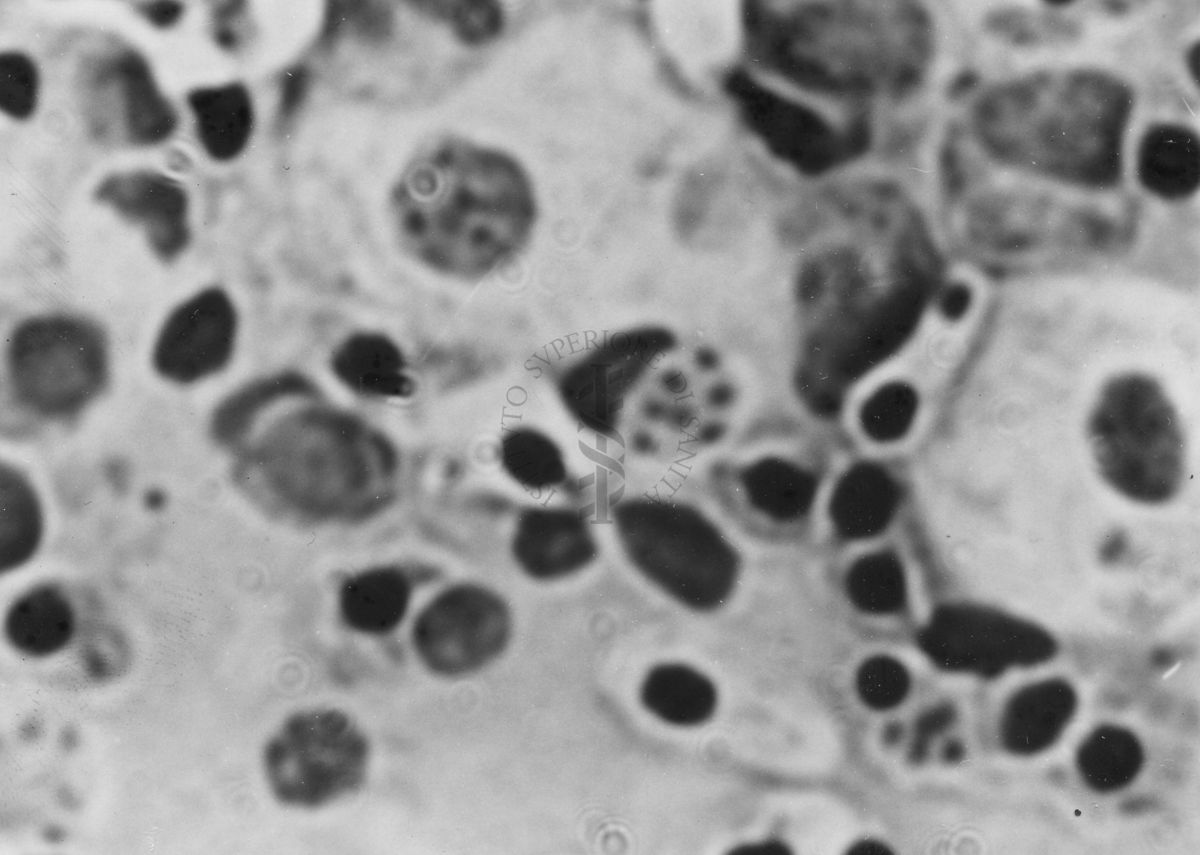

Immagini di Emoprotozoi